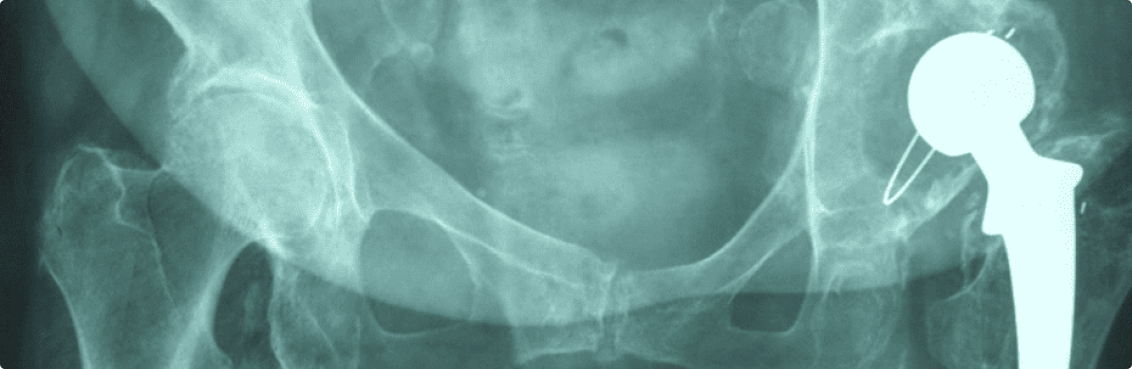

Ολική Αρθροπλαστική Ισχίου με την μέθοδο ASI

Αναθεώρηση Της Ολικής Αρθροπλαστικής Του Ισχίου: Τώρα Και Με Τεχνική Ελάχιστης Επεμβατικότητας ASI

Παρόλο που η ολική αρθροπλαστική ισχίου είναι μια από τις πιο επιτυχημένες χειρουργικές επεμβάσεις στην ορθοπαιδική, ένας σημαντικός αριθμός ασθενών υποβάλλεται σε αναθεώρησή (δεύτερη επέμβαση / επανεπέμβαση) είτε λόγω μηχανικών προβλημάτων (χαλάρωση ή φθορά της πρόθεσης, κακή τοποθέτηση), είτε μικροβιακής λοίμωξης, είτε κατάγματος πέριξ της πρόθεσης.

Παραδοσιακά οι επεμβάσεις αναθεώρησης στο ισχίο απαιτούν εκτεταμένες προσπελάσεις (μεγάλες τομές, μεγάλες κακώσεις στα μαλακά μόρια, μεγάλη απώλεια αίματος) και συνοδεύονται από μεγαλύτερο ποσοστό επιπλοκών σε σχέση με την πρώτη επέμβαση. Στις περιπτώσεις που μόνο ένα τμήμα της πρόθεσης παρουσιάζει πρόβλημα προτιμάται η μεμονωμένη αντικατάστασή του, καθιστώντας την αναθεώρηση λιγότερο χρονοβόρα, με λιγότερες ανάγκες για αίμα και με ταχύτερη αποκατάσταση.

Η τεχνική ελάχιστης επεμβατικότητας ASI (Anterior Supine Intermuscular) εκτός από τη μεγάλη επιτυχία της στις αρχικές επεμβάσεις ολικής αρθροπλαστικής του ισχίου χρησιμοποιείται με άριστα αποτελέσματα και σε περιπτώσεις που είναι αναγκαία η αναθεώρηση μόνο της κοτυλιαίας πρόθεσης εξασφαλίζοντας το μέγιστο των πλεονεκτημάτων της μερικής αντικατάστασης της παλαιάς πρόθεσης.

Με την ASI πρακτικά εξαλείφονται οι ανάγκες μετάγγισης, ο χρόνος αποκατάστασης μειώνεται δραματικά και αποφεύγονται οι επιπλοκές που συνοδεύουν τη μακρά περίοδο ανάρρωσης μετά από εκτεταμένες προσπελάσεις του ισχίου. Τα πλεονεκτήματα της μεθόδου οφείλονται στον ελάχιστο τραυματισμό των μαλακών μορίων γύρω από τη τεχνητή άρθρωση (τα οποία είναι ήδη τραυματισμένα από την προηγούμενη επέμβαση), την καλή ορατότητα που έχει ο χειρουργός κατά την επέμβαση και την άμεση εκτίμηση του μήκους και των δύο κάτω άκρων.

Στην Κλινική Μεγάλων Αρθρώσεων του Ιατρικού Κέντρου Αθηνών με διευθυντή τον κ. Ιωάννη Τσαρούχα έχει πραγματοποιηθεί μεγάλος αριθμός αναθεωρήσεων με την μέθοδο ASI που συνδυάζονται, κατά περίπτωση, με τις αξιόπιστες τεχνικές της κοτυλοπλαστικής και την εισαγωγή μοσχευμάτων στις περιοχές οστικών ελλειμμάτων (impaction grafting, strut grafts κτλ). Ιδιαίτερα, η κοτυλοπλαστική αποτελεί μια δοκιμασμένη μέθοδο για την αντιμετώπιση περιπτώσεων ατελούς διαμόρφωσης της κοτύλης και μεγάλων οστικών ελλειμμάτων . Η επιλογή των ασθενών που μπορούν να υποβληθούν στην επέμβαση αναθεώρησης με ASI γίνεται μετά από λεπτομερή προεγχειρητικό έλεγχο για τον αποκλεισμό της περίπτωσης να υπάρχει μεγάλη φθορά και στη μηριαία πρόθεση ή τα οστικά ελλείμματα της κοτύλης να είναι τόσο μεγάλα, ώστε να χρειάζονται εκτενέστερες προσπελάσεις.